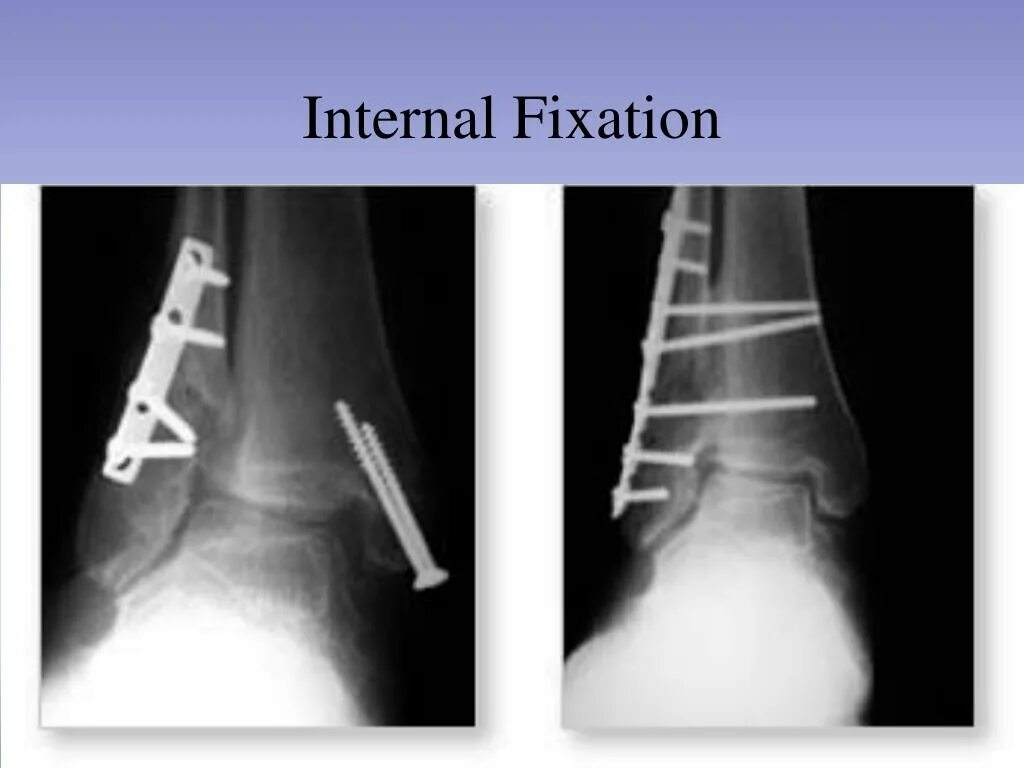

Лодыжка перелом смещение операция пластина